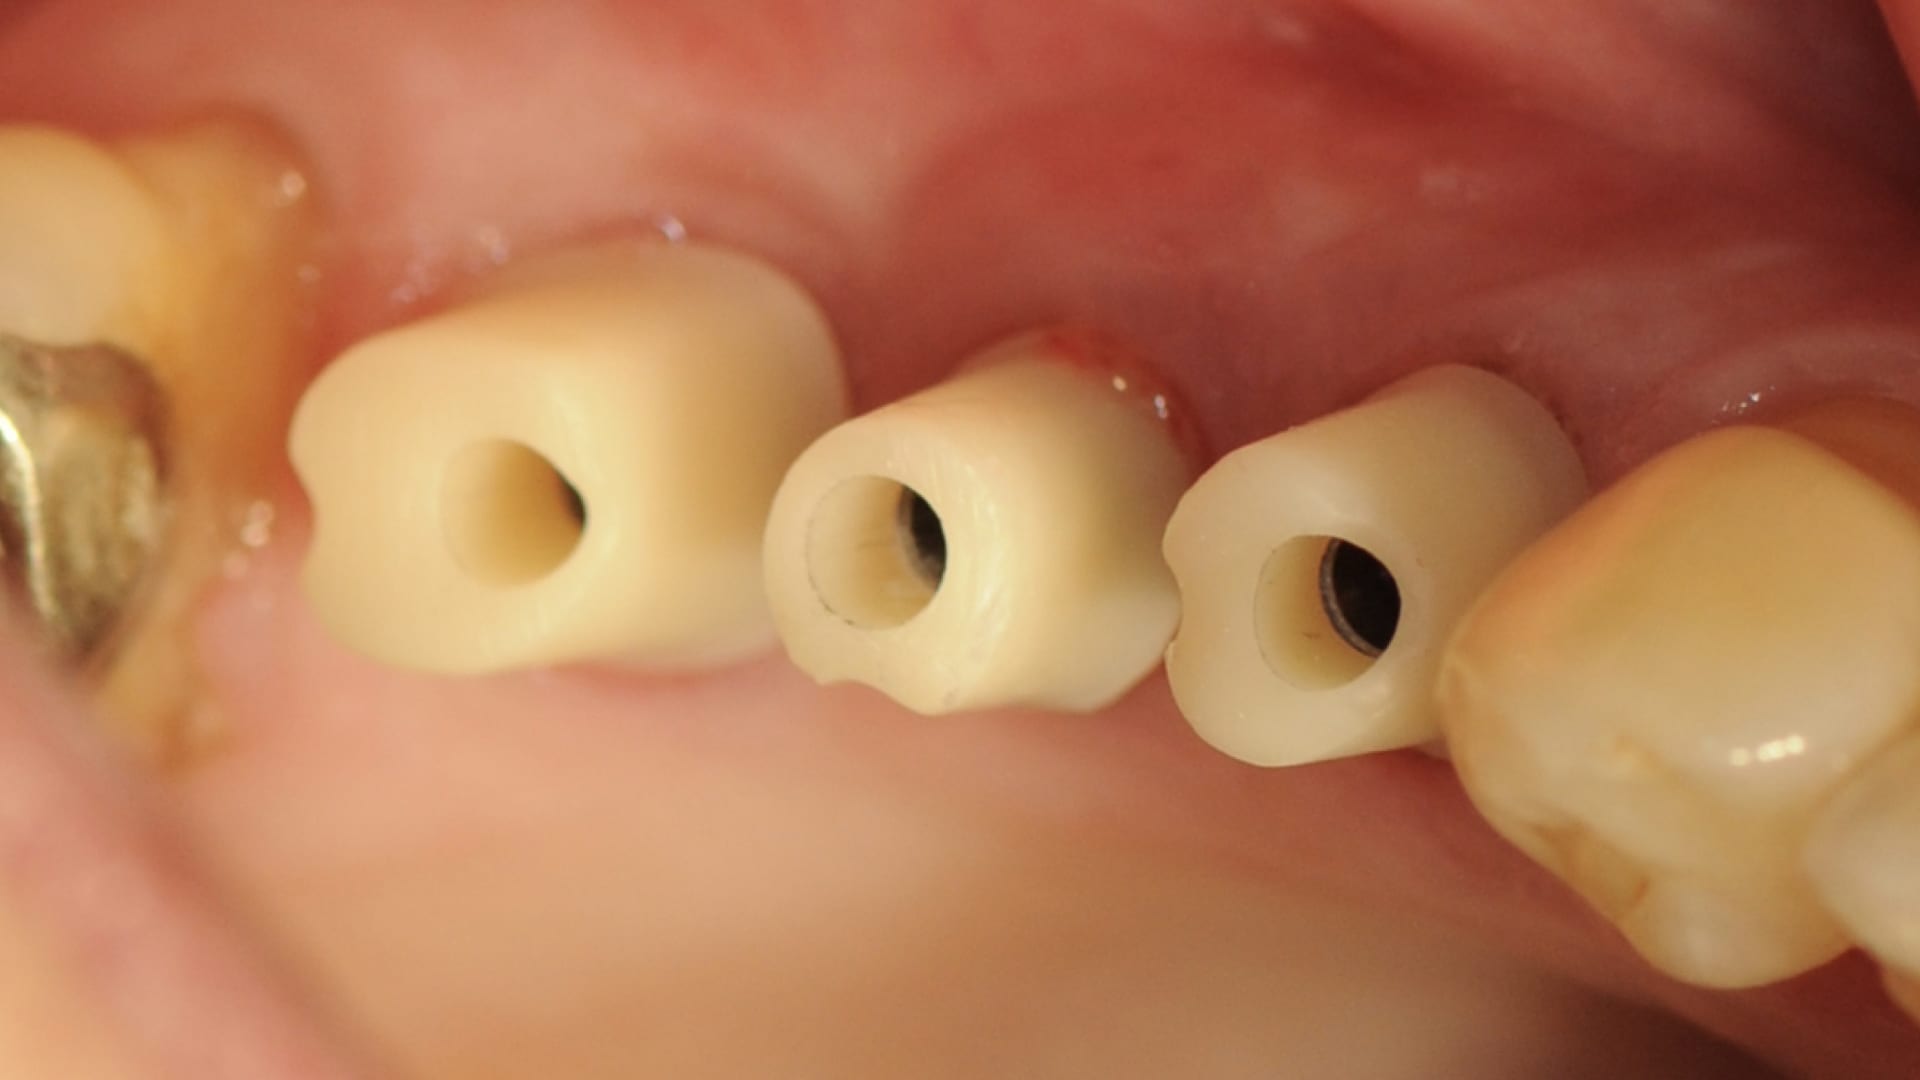

Abb. 17: Okklusalansicht der Hybridabutments in Situ (1)

Abb. 18: Okklusalansicht der Hybridabutments in Situ (2)

Digital trifft analog

Die erstellten digitalen STL-Daten der Modelle wurden in der CAM-Software des 3D-Druckers positioniert und zum Drucker gesendet. In der CAM-Software der Fräsmaschine erfolgte das Nesting der designten Abutments und Verblendkappen in einem Zirkonoxid-Block (Abb. 10 bis 12). Hier endete die digitale Prozesskette im vorliegenden Fall. Die gedruckten Modelle artikulierte das Dentallabor ein. Ebenso wurden die digitalen Laboranloge im Modell mit Pattern Resin fixiert. Die Aufbereitung der Abutments und die damit verbundene Güte der Oberfläche erfolgte nach dem von Rinke et al. erarbeiteten Protokoll. Zur Verbindung von Variobase und Zirkonoxid kam ein Multilink Hybrid-Abutmen zum Einsatz. Im Anschluss erfolgte die keramische Verblendung der anatomisch reduzierten Zirkonoxid-Kappen nach den Vorgaben des intraoralen Scans (Abb. 13) und der Versand in die Praxis (Abb. 14 und 15). Nach dem Einbringen der Abutments auf Klebebasis mit 35 Ncm (Abb. 16 bis 18) wurden die Schraubenkanäle mit Komposit verschlossen. Die definitiven Kronen wurden nach der Ästhetik-, Funktions- und Okklusionsprüfung mit implantlink semi Forte von Detax eingesetzt (Abb. 19 und 20).